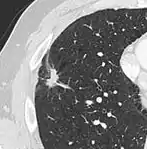

Part solid nodule.[9]